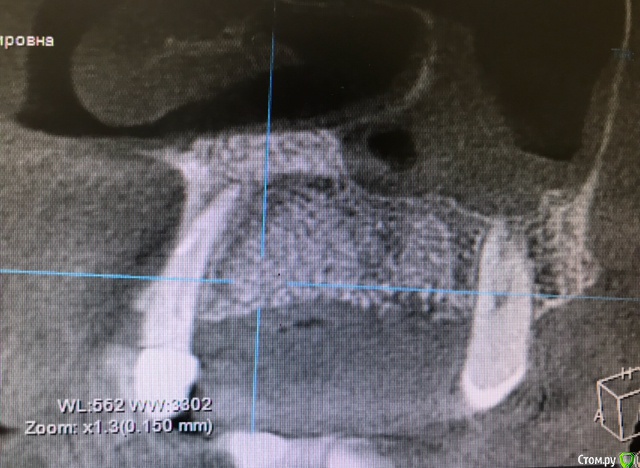

колесников Опубликовано 15 марта, 2019 Автор Поделиться Опубликовано 15 марта, 2019 Вот так выглядит интегрированый графт и соответственно не созревший. Время ожидания примерно равнозначное Ссылка на комментарий

колесников Опубликовано 16 марта, 2019 Автор Поделиться Опубликовано 16 марта, 2019 (изменено) Ну как бы тут все очевидно. Слева стала костью,справа нет. Но должен вам отметить,что даже в случае неудачи (как кажется)потери нет. Задача стояла не увеличить объём для имплантации или укрыть Имплант,а снять напряжение с вершины гребня и дать созреть десне. Имплант в нативной кости,он интегрирован,десна успела созреть за это время,возможно будет не так объёмно как хотелось бы,но у меня в запасе этап раскрытия ,фдм зарос ,есть с чем поработать. Все что не интегрировалось ,лизируется самостоятельно,выскребать ничего не нужно,ещё подождать. Изменено 16 марта, 2019 пользователем колесников Ссылка на комментарий